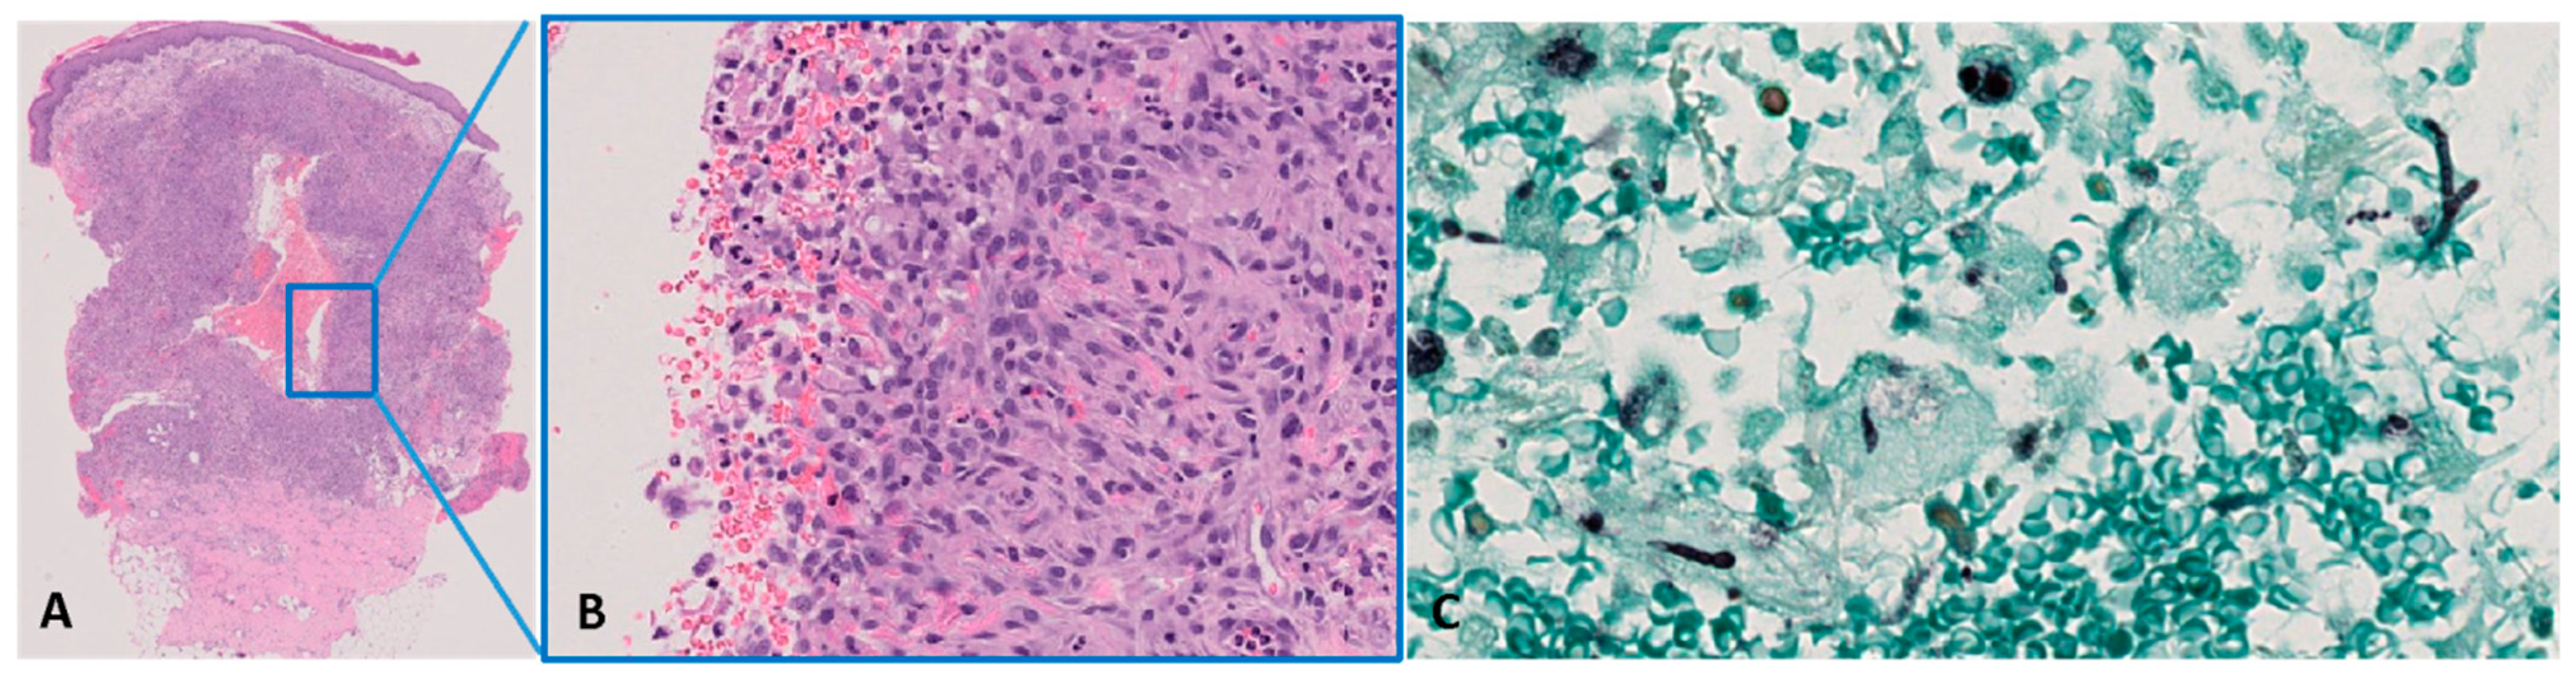

Figure 4.

Histopathological features: (A,B) Granulomatous dermatitis at incisional biopsy (haematoxylin–eosin stain, magnification 10×—(A) and 400×—(B)). (C) Fungal globose yeast-like structures and septate hyphae in the dermis (Grocott stain, magnification ×400).